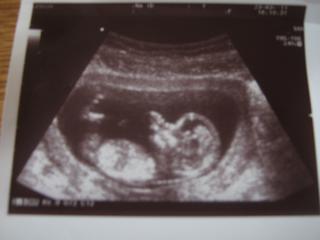

@jahu hezká fotečka

@fram jj nožky mělo křížem a ručičku před obličejíčkem doufám ,že mi za měsíc ukáže co má mezi nožkama 😀 Farm když dělají testy berou krev na VV nemusím být na lačno že ne??

jahudko-tak ať se zájemcům byteček moc líbí a okamžitě berou.mimísek je nádhernej 😉

@jahudka80 Super zprávy. Krásnej mrňousek.

ahoj holky jane84 super gratuluju jsi rada vid? lucko.krajcarova hezka nova fotka co tu mas slusi ti to na ni....jahudko no tak to je pech, ze neprisli, ale jeste, ze ti to alespon zavolali....taky krasna fotecka mimiska nechas si rict co to bude? dneska mam nadherny pocasi venku ale stehujem veci co tu mame do uschovny protoze pristi tyden se vracime do californie tak se tesim, ale i ne......tesim v tom ze se budu pomalu pripravovat na svatbu a netesim, protoze hawaii je proste hawaii raj na zemi.........holky ty chlapi jsou hrozny kdyby mohli tak se vemou doma v obyvaku reknou ano a tim to zhasne......ten muj si mysli, ze vsechno je hrozne lehky.......ma to na haku je to proste chlap...no ja mu dam 😀 😀 😀 😀 taky se tesim k tomu doktorovi.......a novej ridicak si musim udelat protoze mi starej uz propadava no mam toho dost a v kvetnu cesko juuuppiiii uz se tesim, protoze az priletim tak s mamkou jedem pro jejich noveho pejska stenatko meli pred tim toho 17 letyho ale ten zemrel pred 3 rokama tak mamka jde do duchodu tak rozhodla, ze chce noveho pejska ale ja s ni budu muset zajet pro neho nebo ni jelikoz tata nas nema o tom ani pomysleni jeeee ten se posere hahahahahah tak jo jsem se nejak rozepsala preju vam krasnej den holky....jooooo kdyby jste nekdo vedela o stenatkach fenka nebo pes do 3500Kc mensiho vzrustu dejte vedet ja koukam na www.bazos.cz tak pa